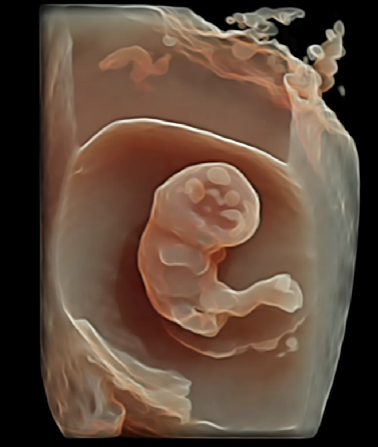

4、9大胎儿核心部位独立成像

E10独有的表面模式、血管模式、组织血管透明模式等智能诊断模式,对胎儿的体表、内脏、血管、骨骼等9大核心部位独立成像,全面弥补传统系统四维彩超在检测范畴及精准度的局限性。